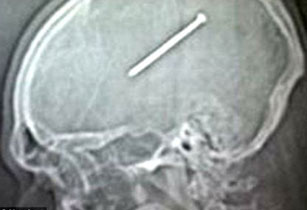

ԱՄՆ-ի Իլինոյս նահանգի բնակիչ Դանթե Աութուլոն շինարարական աշխատանքի ժամանակ մեխ կրակող ատրճանակով պատահմամբ կրակել է դեմքի ուղղությամբ, և մոտ 9 սմ-անոց մեխը մխրճվել է նրա գանգի մեջ։ Այս մասին գրում է «All Voices» լրատվական գործակալությունը։

Զարմանալին այն է, որ Աութուլոն 3 օր բուժօգնության չի դիմել՝ պնդելով, թե լուրջ ցավեր չի էլ զգացել.

«Շատերի համար զարմանալի է, բայց ես իսկապես լուրջ ցավեր չեմ ունեցել։ Մի քիչ գլուխս էր պտտվում, այլապես բժշկի չէի դիմի»,-ասել է Դանթեն։

Բժիշկները մեխը հեռացրել են, բայց մինչև հիմա ապշած են՝ ինչպես կարելի է նման վիճակում երեք գիշեր գլուխը հանգիստ դնել բարձին։

9 սմ-անոց մեխը 3 օր մնացել է ամերիկացու գանգի մեջ